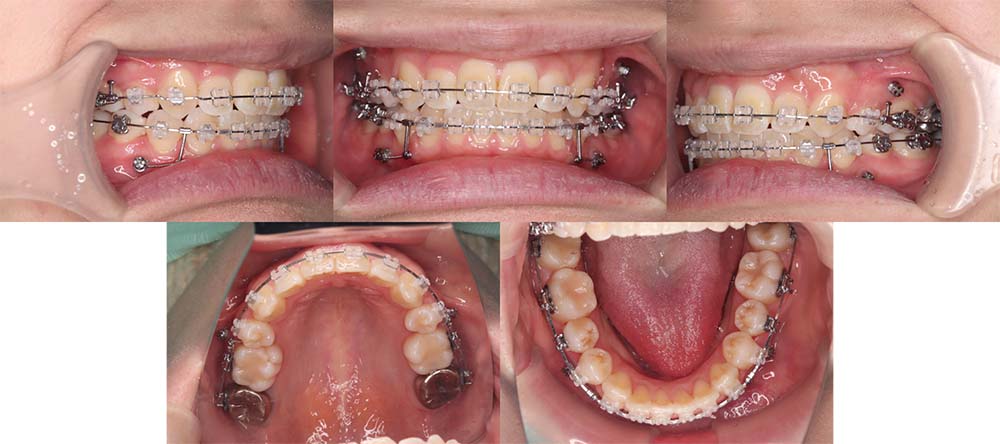

| 症例分類 | 上顎前突、叢生、シザースバイト |

| 診断名 | 右上7のシザーズバイトを伴う上下重度叢生skeletal2 |

| 主訴 | 歯並びが悪くて全体的にガタガタ |

| 年齢 | 19歳11ヶ月 |

| 性別 | 女性 |

| 抜歯部位 | 上顎左右と右下の第一小臼歯、左下の第二小臼歯(4本)、上顎右側第二大臼歯 |

| 使用装置 | 裏側のワイヤー装置 |

| 治療期間 | 2年11ヶ月(5ヶ月程度来院出来ない期間あり) |

| 保定装置 | 固定式保定装置、取り外し式保定装置(8時間) |

| 費用 |

[検査・診断料] ¥49,500 [基本施術料] ¥1,331,000 [調整料] ¥5,500/回 [抜歯] ¥5,500/本 [保定装置] ¥55,000(税込) 抜歯や虫歯治療は他院にて費用が別途かかります。(抜歯¥4,000〜10,000/本)

上下の重度叢生と上の歯が前方にあり上顎両側の第一小臼歯と下顎右側第一小臼歯、下顎左側第二小臼歯、上顎右側第二大臼歯(上顎右側親知らずを咬合に使用)を抜去して上下リンガルで治療を行いました。 左上の第二大臼歯部の咬合が深かったため、一時的に頬側に装置をつけさせて頂きました。裏側に装置を装着すると噛み合わせを浅くするためのバイトアップがかなりの量が必要になり咬みづらくなってしまうためです。

5ヶ月程度来院が出来なかった期間がありましたが、問題なく治療を終了することができました。